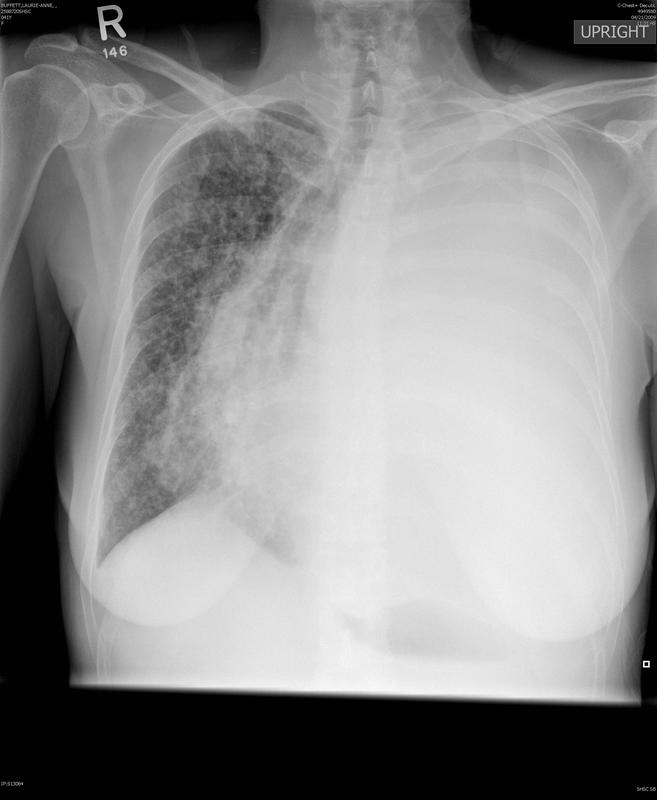

Gallery Lung Cancer Miscell Ca tension

Ca tension